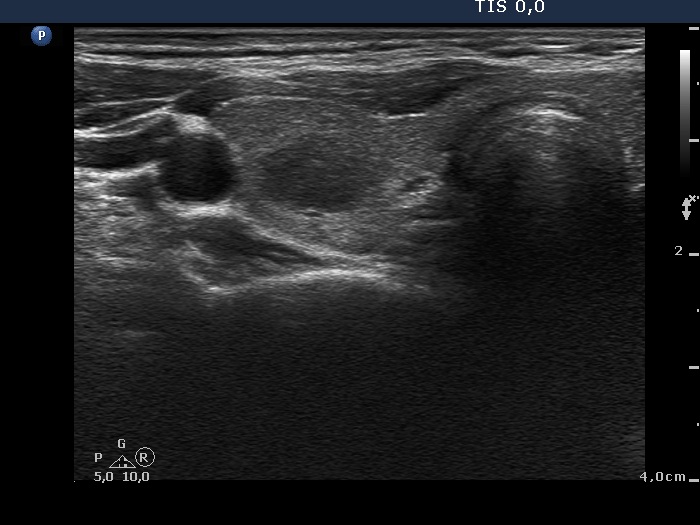

Ultrasonography. The thyroid was echonormal. There was moderately hypoechogenic nodule with blurred borders in the central part of the right lobe. A cystic nodule having echonormal solid part was found in the lower pole of the right lobe. The left lobe also has a cystic nodule.